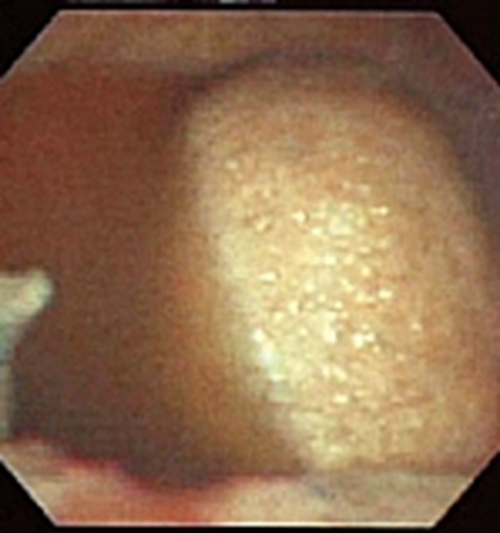

結核性胸膜炎胸腔鏡

結核性胸膜炎胸腔鏡的